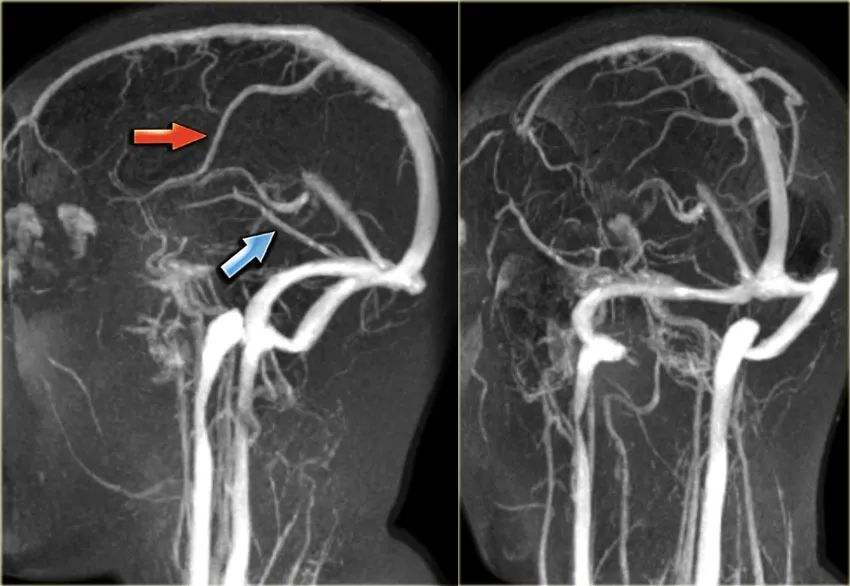

磁共振血管造影是一种利用核磁的流空效应来显示血管的新技术,其操作过程主要包括以下步骤采集图像资料首先,通过磁共振设备采集一系列连续薄层的断面图像资料这些图像资料是后续进行血管重建的基础图像后处理采集完图像资料后,需要进行后处理常用的后处理方法包括重建,其中最大信号强度投影法是最。

MRA磁共振血管造影在脑血管成像方面具有明显优势,其图像质量更为清晰,能够提供详细的血管结构信息,对于诊断脑血管疾病具有重要意义相比之下,TCD经颅彩色多普勒虽然在评价颅内动脉血流速度有无涡流等动态数据方面具有独特优势,但其检查结果容易受到操作者技术水平的影响尽管MRA在成像效果上更。

磁共振血管造影是一种无创性的血管成像方法以下是关于磁共振血管造影的详细解释成像原理磁共振血管造影利用磁共振现象从人体中获得电磁信号,并通过这些信号重建出人体血管的信息它是对血管和血流信号特征进行显示的一种技术优势特点该方法无需电离辐射,避免了放射性损伤同时,它也不需要依赖造。

磁共振血管造影对患者来说是非常安全的,基本上没有危害以下是具体的解释非损伤性技术MRA是利用核磁特殊的流动效应进行成像,不需要通过动脉或静脉内注射造影剂,因此是一种完全的非损伤性血管造影技术无辐射与X射线或CT等放射性检查不同,MRA不产生电离辐射,因此不会对患者造成辐射伤害对比。